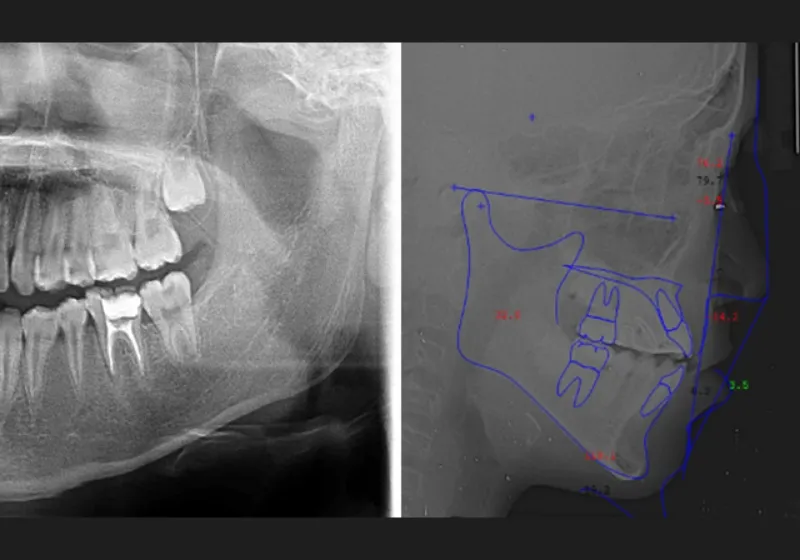

精密検査

患者さまの口や顎の情報を取得するため、3Dスキャナーによる歯型の採取や顔貌・口腔内の写真撮影、パノラマやセファロのレントゲン撮影などの精密検査を実施します。

診断と治療計画の説明

精密検査の結果をもとにお口の状態を診断し、患者さまに適した治療計画を立案してご提案します。選択する治療法や装置の種類によって治療期間や費用が異なるため、患者さまのご希望を考慮し、より良い治療をご提案します。疑問点やご要望があれば遠慮なくお知らせください。